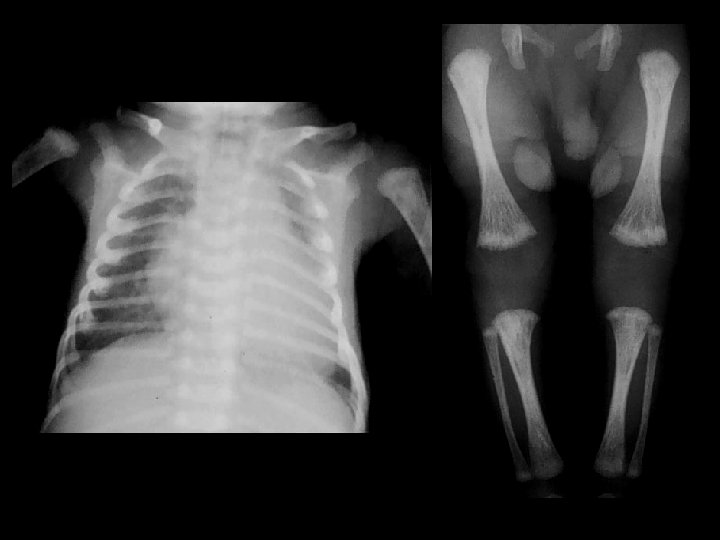

Osteogenesis Imperfecta Type II • Findings: – multiple fractures, bowing and short ribbon-like bones • Type II - lethal - “ribbon bones” and fractures too numerous to count • Disturbances in type I collagen – lack of normal collagen – osteoperosis – fractures – blue sclera • ddx: – NONE! – This is an Aunt Minnie!